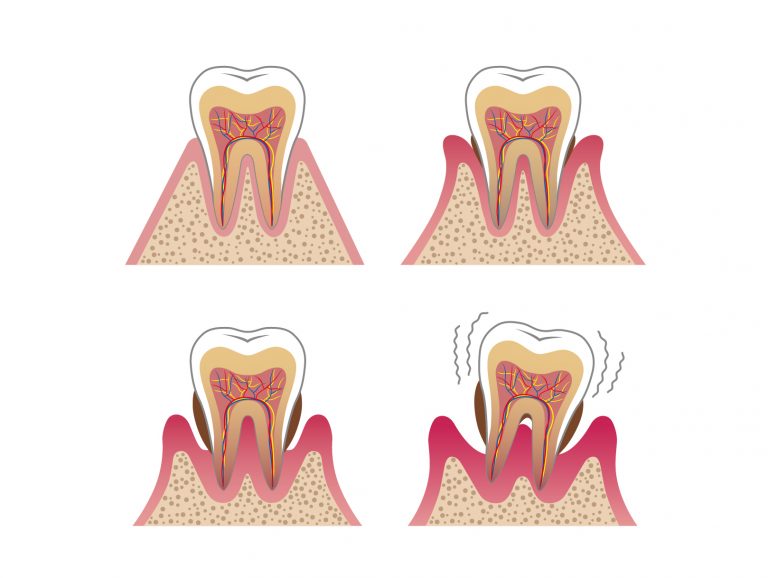

歯周病の始まりから歯の脱落に至るまで、歯周病の進行具合を詳しく説明します。

症状のない初期段階:歯肉炎

歯肉炎は、歯周病の最も初期の段階で、炎症が歯茎のみに限られている状態です。

プラーク内の細菌毒素によって歯茎が赤く腫れたり、歯磨きやフロスで出血しやすくなったりしますが、ほとんどの場合、痛みなどの自覚症状はありません。

歯槽骨の破壊はまだ始まっておらず、歯周ポケットの深さも1〜2mm程度浅さです。初期段階であれば、適切なブラッシングと歯科でのクリーニングにより炎症を鎮めることも可能です。

破壊が始まる中期段階:軽度〜中等度歯周炎

軽度〜中等度歯周炎は、歯肉炎から進行し、歯を支える組織の破壊が始まった状態です。

歯肉の炎症が歯茎の下、歯の根を覆う歯根膜や歯槽骨にまで波及し、骨が溶け始めます。骨が溶けることによって、想定される歯周ポケットの深さは3〜6mm程度です。

症状が進むと、歯茎からの出血や腫れが頻繁になり、口臭が強くなります。さらに進行すると、歯周ポケットの奥で細菌が増殖し、押すと膿が出たり、歯槽骨の吸収により歯がわずかにグラグラしたりする症状が現れます。

中程度の症状では自然治癒は難しくなり、専門的な治療が必要です。

歯を失う末期段階:重度歯周炎

重度歯周炎は、歯周病の最終段階であり、歯槽骨が大きく失われた状態です。

重度まで進むと、炎症が広範囲に及び、歯槽骨が半分以上、あるいはほとんど溶けてしまいます。歯周ポケットは6mm以上にまで深くなり、歯の根元が露出することから、その見た目は「歯が長くなったのでは?」と勘違いするほどです。

最も深刻な症状は、歯槽骨が歯を支えきれなくなり、歯が激しくグラグラと動揺することです。強い口臭や、常に歯茎から膿が出続ける状態も多く見られます。最終的には、歯が自然に抜け落ちるか、やむを得ず抜歯が必要となり、歯を失うことになります。この段階では、通常の治療は難しいです。専門的な外科処置が中心となります。